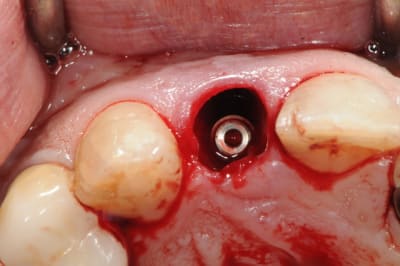

7: mise en place de l'implant.

oh, je sais! les mauvaises langues diront que j'avais dit que je n'implantais pas sur les secteurs infectés. mais bon, là c'est un secteur esthétique. faut bien des exceptions pour confirmer la règle, non ?

eh ben voilà! me v'la coincé!

l'implant à beau faire 14 mm de long, avec le granulome qu'il y avait au bout de la racine, j'ai pas assez de stabilité primaire pour une mise en charge immédiate comme prévue.

donc soit je dégage l'implant, soit je considère qu'il est bien placé mais il faut le protéger, lui et le matériaux de comblement.

j'opte pour un greffon de G.A libre.

quel diamètre ton implant D57? c'est un 3.4mm, non?

si oui, n'aurais-tu pas eu intérêt à poser un 4 en condensant/expansant l'os avec des ostéotomes et/ou les meissinger pour gagner en stabilité primaire et rendre la MCI possible?

je dis çà juste parce que ton implant semble bien à l'aise dans son alvéole...

c'est un AXIOM 4mm de diamètre.

prendre plus gros serait déraisonnable (à mon avis...)